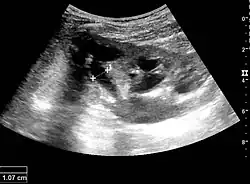

With US, larger stones (>5–7 mm) within the kidney, i.e., in the calyces, the pelvis and the pyeloureteric junction, can be differentiated, especially in the cases with accompanying hydronephrosis (Figure 18 and Figure 19). Hyperechoic stones are seen with accompanying posterior shadowing. Additional twinkling artifacts below the stone can often be seen using Doppler US. Large stones filling the entire collecting system are called coral stones or staghorn calculi and are easily visualized with US (Figure 20). Stones in the ureters are usually not visualized with US due to the air-filled intestines obscuring the insonation window. However, ureteral stones near the ostium can be visualized with a scan position over the bladder. An exam of the ureteric orifices and the excretion of urine to the bladder can be performed by inspecting the ureteric jets in the bladder with color Doppler US.

Figure 19. Centrally located stone with posterior shadowing. No hydronephrosis is present. Measurement of kidney length on the US image is illustrated by '+' and a dashed line.[1]